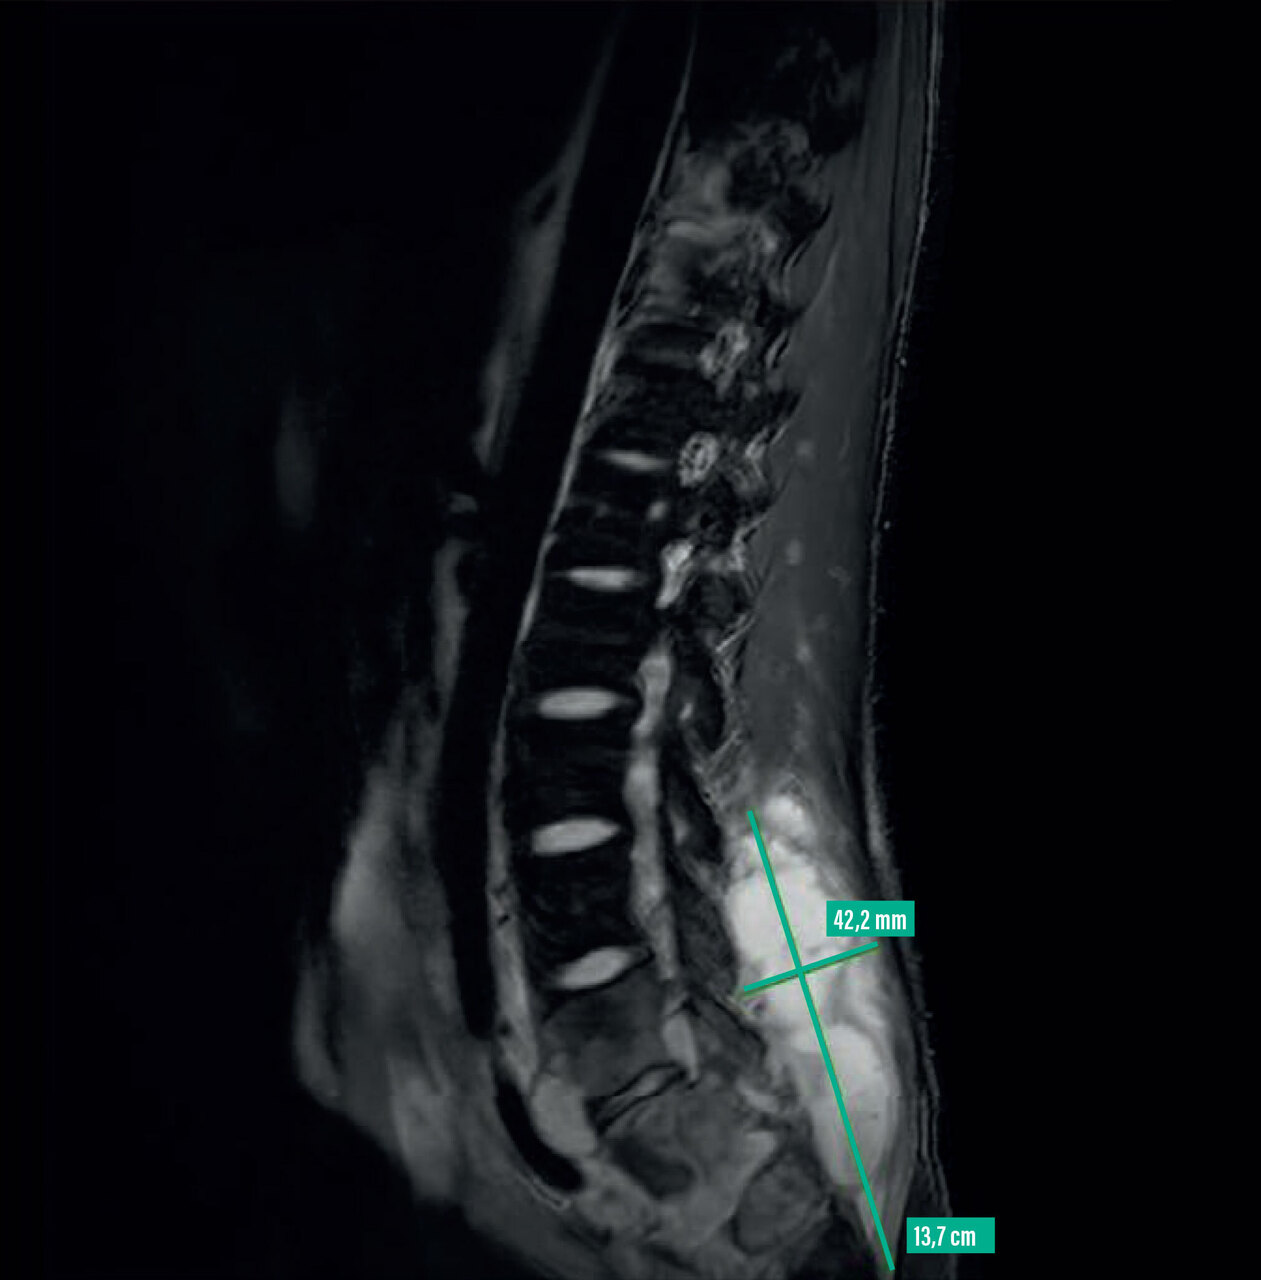

Un homme âgé de 22 ans, originaire du Congo, en France depuis un an, consulte pour une perte de poids de 10 kg en six mois, de la fièvre et des sueurs nocturnes apparues depuis trois mois. Il se plaint de lombalgies et, depuis un mois, d’une tuméfaction paravertébrale droite. Une imagerie par résonance magnétique est réalisée et un abcès paravertébral est ponctionné.

L’imagerie par résonance magnétique (IRM) montre de multiples abcès paravertébraux de la région lombo-sacrée, une spondylite de la vertèbre T10 avec extension épidurale et compression du sac dural. La ponction d’un abcès paravertébral détecte, par test PCR, l’ADN du complexe Mycobacterium tuberculosis et l’absence de mutation en faveur d’une résistance à la rifampicine et à l’isoniazide. Une quadrithérapie antituberculeuse est débutée, en association à une corticothérapie du fait de la compression épidurale.